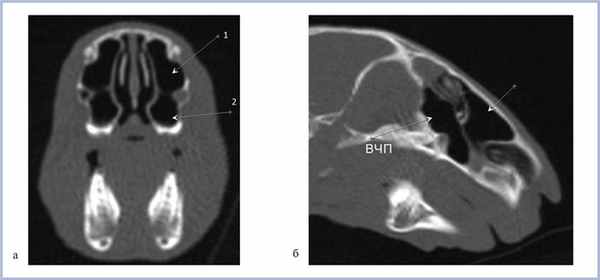

На рис. 2 представлены верхнечелюстные пазухи кролика в возрасте 3 нед в различных проекциях; на рис. 3 в возрасте 6 мес. Таким образом, у кроликов уже в возрасте 3 нед определяются сформированные верхнечелюстные пазухи.

Рис. 2. Компьютерная томография околоносовых пазух кролика в возрасте 3 нед.

Рис. 3. Компьютерная томография околоносовых пазух кролика в возрасте 6 мес.